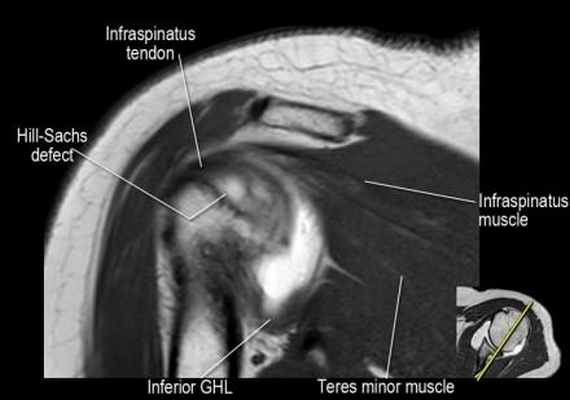

- обратите внимание на верхние отделы суставной губы и прикрепление верхней плече-лопаточной связки. На данном уровне ищется SLAP-повреждение (Superior Labrum Anterior to Posterior) и варианты строения в виде отверстия под сутавной губой (sublabral foramen - подгубное отверстие). На этом же уровне по задне-боковой поверхности головки плечевой кости визуализируются повреждение Хилл-Сакса.

- волокна сухожилия подлопаточной мышцы, создавая бицепитальную борозду, удерживают сухожилие длинной головки двуглавой мышцы. Изучите хрящи.

- обратите внимание на небольшое повреждение Хилл-Сакса